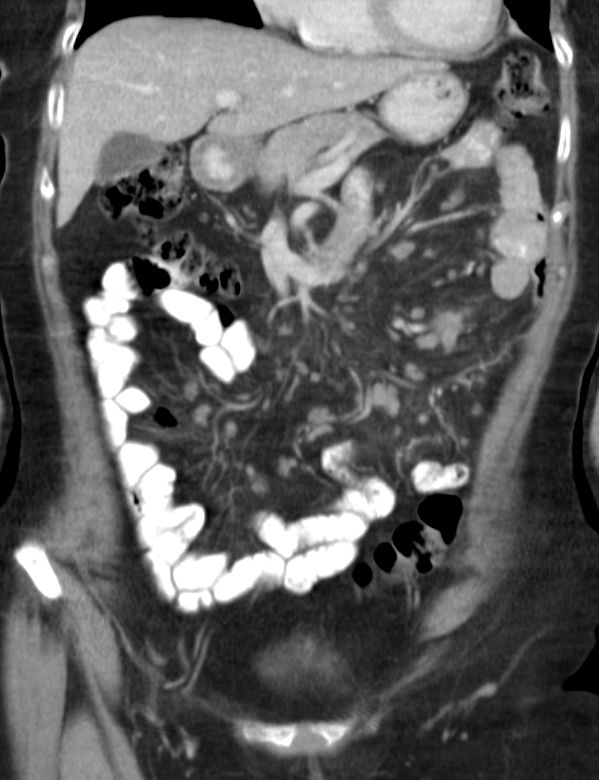

Mesenterialer Bulk |

77-jähriger Mann mit einem abdominalen Tumor und Stenosesymptomatik. Im Dünndarmresektat mit Mesenterialwurzel ein follikuläres Lymphom Grad II-IIIa, FLIPI-Score 2.![]() |

![]() |

![]() | |